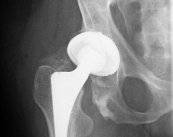

La artrosis de cadera es un padecimiento crónico y para el tratamiento de casos muy avanzados se puede indicar el reemplazo de cadera. Se trata de un procedimiento quirúrgico extremadamente reglado y estandarizado, el cual debe ser realizado por un equipo de especialistas para garantizar los mejores resultados. Conozca los detalles sobre esta intervención